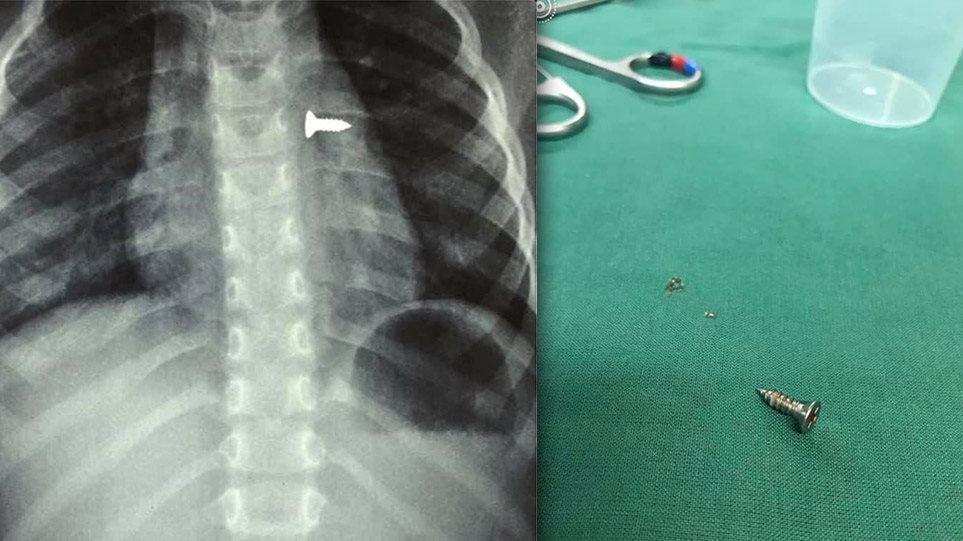

Αμέσως έβγαλε ακτινογραφίες, που έδειξαν πως η βίδα βρισκόταν στον αριστερό του πνεύμονα, με τις εικόνες να είναι σοκαριστικές.

Οι γιατροί οδήγησαν το κορίτσι στο χειρουργείο και μετά από αρκετή ώρα κατάφεραν να αφαιρέσουν την βίδα.

Ο κ. Προκοπάκης σε ανάρτησή του στα social media ανέφερε: «Πολύ επείγον χειρουργείο! Πριν από λίγο. Αφαίρεση βίδας από αριστερό βρογχικό δέντρο τρίχρονου κοριτσιού. Πολύ επικίνδυνο…».